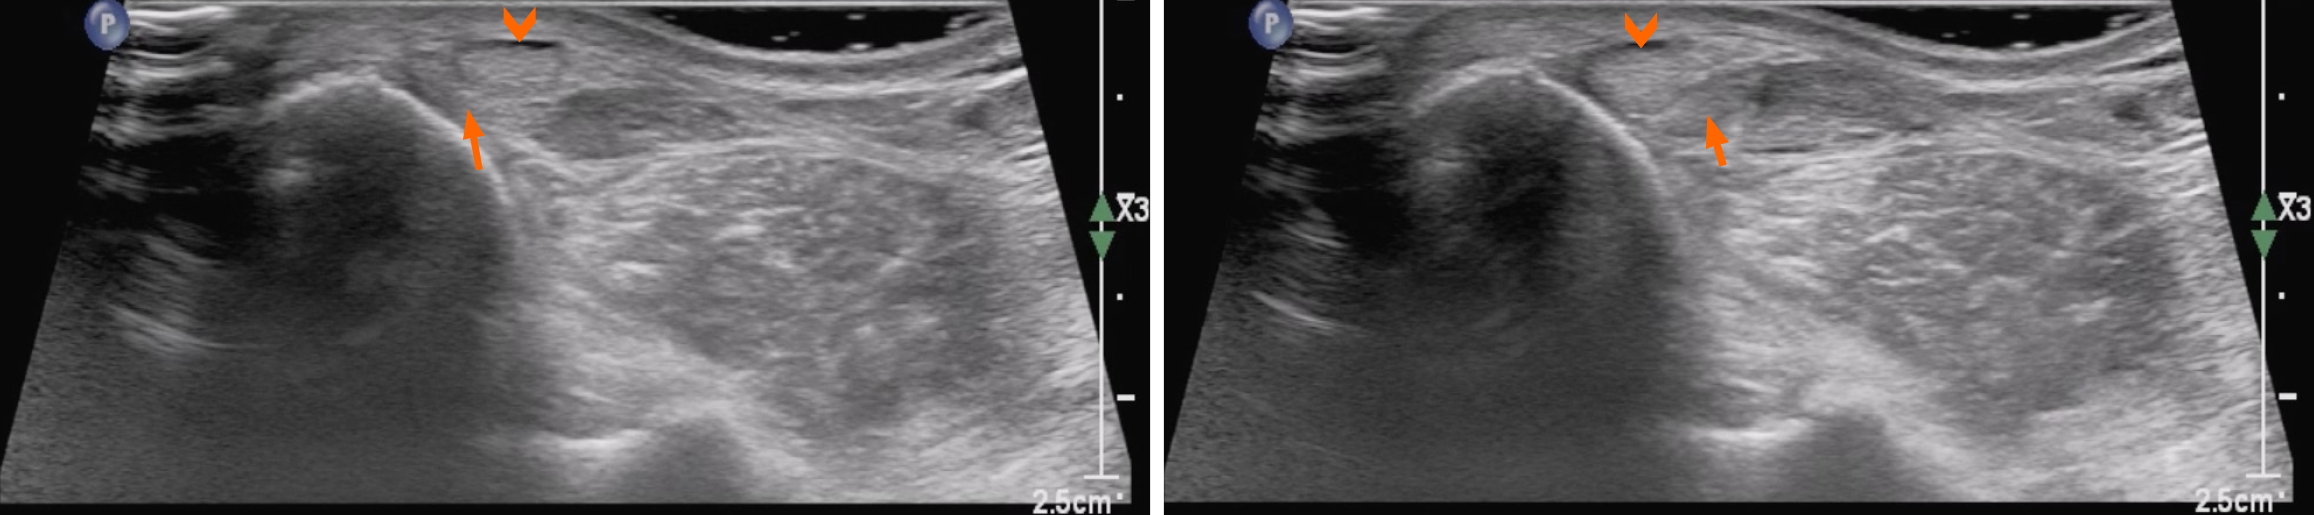

Figure 5 Post-repair intraoperative pictures of the superior peroneal retinaculum (arrowhead).